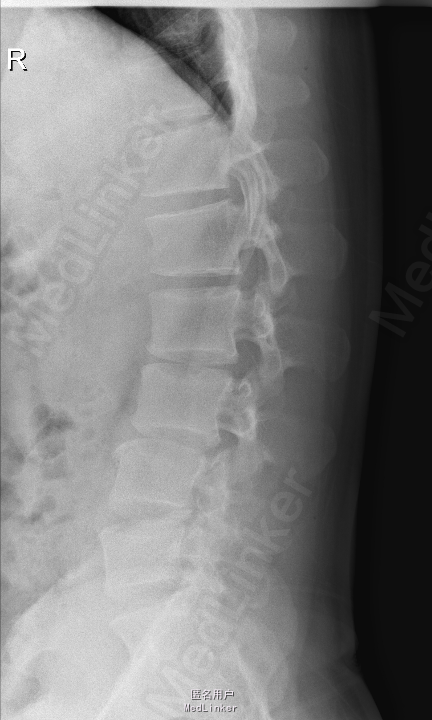

查体:腰部叩痛,腰部活动受限,左侧膝内侧、小腿外侧、内踝、足部感觉减退,右侧小腿、足背感觉减退,屈髋、伸膝、踝背伸肌肌力左侧4级,右侧4-5级,踇背伸、跖屈肌肌力左侧3-4级,右侧4级,双侧膝腱反射+,跟腱反射+,双侧巴氏征阴性,直腿抬高试验左侧40°阳性,右侧阴性。 辅助检查: X-ray:腰椎退行性变,多节段不稳 CT:腰椎间盘突出并椎管狭窄伴钙化,腰2-3,3-4,4-5,腰5骶1 MR:腰椎间盘突出并椎管狭窄,腰2-3,3-4,4-5,腰5骶1 上传受限无法全部上传,见谅

诊断:腰椎间盘突出症并椎管狭窄 处理: 1、完善相关辅助检查,明确诊断,有无手术指证; 2、完善手术评估,有无手术禁忌,手术风险及并发症; 3、在全麻下行腰椎后路多节段减压椎间植骨融合内固定术 4、腰2-3,腰3-4行开窗减压,腰4-5,腰5-骶1行椎间Cage植骨融合